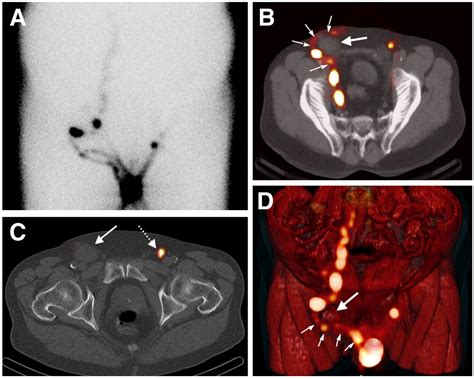

During a consultation, your physician will likely perform a physical examination to check the size, texture, and location of the node. They may also order blood tests, imaging studies such as an ultrasound, or in some cases, a biopsy to determine the exact cause of the swelling. Early diagnosis is key to effective management, regardless of whether the cause is a simple infection or something requiring more intensive treatment.